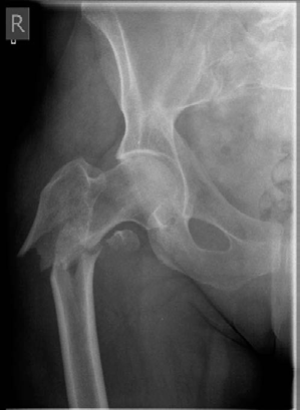

Lower limb Trauma Structured oral examination question 7 A 78-year-old woman fell out of her bed and sus- tai…